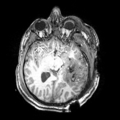

Revision as of 16:33, 8 January 2012 by Dpace (talk | contribs) (Created page with '__NOTOC__ <gallery> Image:PW-SLC2012.png|Projects List Image:MP_RAGE_PRECONTRAST.png‎|An example T1 weighted image from a patient with TBI…')